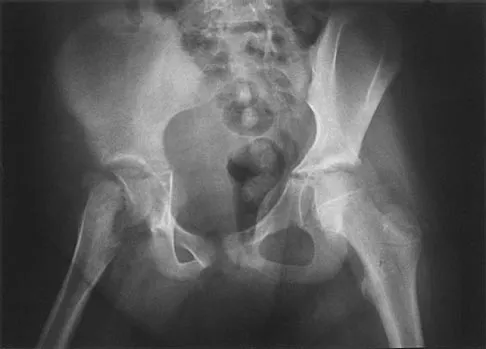

Figures 40a and 40b show the pre- and postoperative radiographs of an 82-year-old woman with bilateral hip pain who has had staged total hip arthroplasties. To minimize potential injury to the sciatic nerve at the time of surgery, the surgeon should

Explanation

To improve hip biomechanics and secure more suitable bone for acetabular fixation, the true acetabulum is often resurfaced in patients who have developmental dysplasia of the hip, thus lowering the hip center and lengthening the leg. Acute lengthening of more than 3 cm will place excessive tension on the sciatic nerve and require a femoral shortening to avoid sciatic nerve injury. The other maneuvers will not relieve sciatic nerve tension because of limb lengthening. Koval KJ (ed): Orthopaedic Knowledge Update 7. Rosemont, IL, American Academy of Orthopaedic Surgeons, 2002, pp 430-431.